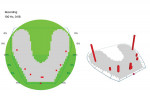

This was an astonishing and highly unexpected development, and the clinician proceeded to try to determine a cause for the problem in order to correct it. After several diagnostic tests were conducted, an OccluSense measurement was taken, which revealed that the patient's occlusion was completely unbalanced (Figure 11) and unprotected. While the OccluSense had not been used at the initial delivery appointment, the clinician did check the occlusion before dismissing the patient. However, because the patient had a complete mandibular denture, the occlusion that he demonstrated at his prosthesis delivery must have been different from the occlusion shown at this emergency appointment.

Utilizing the OccluSense for guidance, the clinician equilibrated the patient's occlusion and was able to create a balanced and protected occlusion (Figure 12). After the patient was in the temporary prosthesis for several weeks, he confirmed that the occlusion functioned well. At that point, a new final full-arch prosthesis was delivered to the patient. This new prosthesis is currently functioning very well and the patient's occlusion has been corrected. The OccluSense provides invaluable information, especially when it relates to fixed or removable full-arch prostheses, turning long and frustrating occlusal equilibrations into predictable appointments.